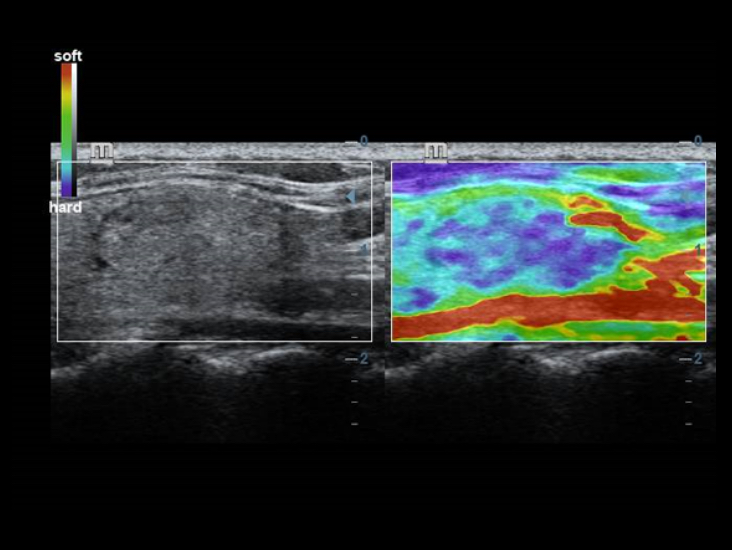

–ö–Μ–Α―¹―¹–Η―΅–Β―¹–Κ–Η–Β ―²–Β―Ö–Ϋ–Ψ–Μ–Ψ–≥–Η–Η –¥–Μ―è –Ω–Ψ–Μ―É―΅–Β–Ϋ–Η―è –Η –Ψ–±―Ä–Α–±–Ψ―²–Κ–Η –Η–Ζ–Ψ–±―Ä–Α–Ε–Β–Ϋ–Η–Ι: –Ω–Ψ–≤―΄―à–Β–Ϋ–Η–Β –Κ–Α―΅–Β―¹―²–≤–Α –¥–Η–Α–≥–Ϋ–Ψ―¹―²–Η–Κ–Η

–ë–Μ–Α–≥–Ψ–¥–Α―Ä―è –Ω―Ä–Η–Φ–Β–Ϋ–Β–Ϋ–Η―é –Κ–Μ–Α―¹―¹–Η―΅–Β―¹–Κ–Η―Ö ―²–Β―Ö–Ϋ–Ψ–Μ–Ψ–≥–Η–Ι –Ψ–±―Ä–Α–±–Ψ―²–Κ–Η ―¹–Η–≥–Ϋ–Α–Μ–Α, –Κ–Ψ―²–Ψ―Ä―΄–Β –±―΄–Μ–Η –Ζ–Α–Η–Φ―¹―²–≤–Ψ–≤–Α–Ϋ―΄ –Η–Ζ ―¹―É―â–Β―¹―²–≤―É―é―â–Η―Ö ―É–Μ―¨―²―Ä–Α–Ζ–≤―É–Κ–Ψ–≤―΄―Ö ―¹–Η―¹―²–Β–Φ, DC-40 ―¹ Full HD –Ω―Ä–Β–¥–Μ–Α–≥–Α–Β―² –≤―΄―¹–Ψ―²–Ψ–Β –Κ–Α―΅–Β―¹―²–≤–Ψ –¥–Β―²–Α–Μ–Η–Ζ–Α―Ü–Η–Η –Ω–Ψ–Μ―΅–Α–Β–Φ―΄―Ö –Η–Ζ–Ψ–±―Ä–Α–Ε–Β–Ϋ–Η–Ι.

- iClear (―²–Β―Ö–Ϋ–Ψ–Μ–Ψ–≥–Η―è –Ω–Ψ–¥–Α–≤–Μ–Β–Ϋ–Η―è –Ζ–Β―Ä–Ϋ–Η―¹―²–Ψ―¹―²–Η)

- PSH (–≥–Α―Ä–Φ–Ψ–Ϋ–Η―΅–Β―¹–Κ–Α―è –≤–Η–Ζ―É–Α–Μ–Η–Ζ–Α―Ü–Η―è ―¹ ―³–Α–Ζ–Ψ–≤–Ψ–Ι –Η–Ϋ–≤–Β―Ä―¹–Η–Β–Ι)

- iBeam (―²–Β―Ö–Ϋ–Ψ–Μ–Ψ–≥–Η―è –¥–Μ―è –≤–Η–Ζ―É–Α–Μ–Η–Ζ–Α―Ü–Η–Η ―¹ –Ω―Ä–Ψ―¹―²―Ä–Α–Ϋ―¹―²–≤–Β–Ϋ–Ϋ―΄–Φ –Κ–Ψ–Φ–Ω–Α―É–Ϋ–¥–Η–Ϋ–≥–Ψ–Φ)